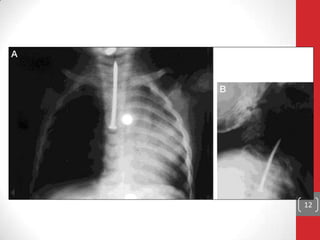

Iekšējas traumas:

• Svešķermeņu iedarbības, ārstniecisku manipulāciju (piem.,

intubācijas) rezultātā.

• Nav bīstami, izņemot balsenes skrimšļu hondroperihondrīta

attīstības iespēju, ilgstošas intubācijas gadījumā var būt

balsenes stenoze.

12

Diagnostika: anamnēze, apskate, RTG, prognoze atkarīga no

traumas lokalizācijas, veida (nobrāzums, dūriens, izguējums),

ilguma, klīnikas.

Ārstēšana: jāņem vērā anamnēze, ja ir abscess ārējā balsenes

daļā, tas jāatver, smagos gadījumos jāveic traheostomija, plaša

spektra a/b.